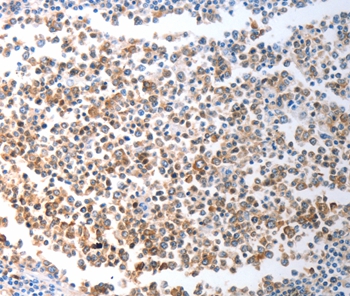

基因名

GPR15

别名

GPR15;G-Protein coupled receptor 15